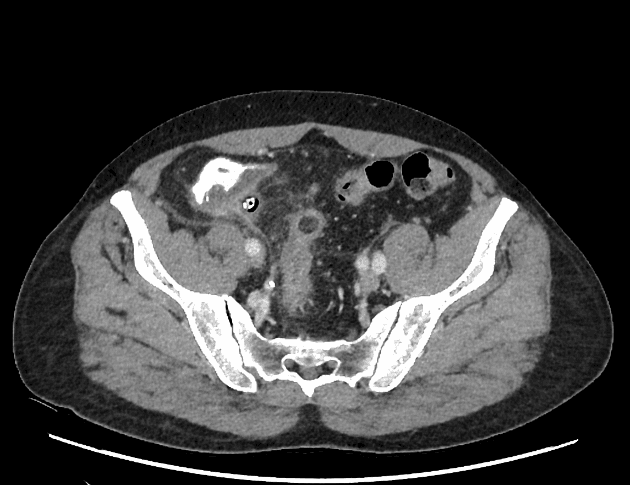

Acute appendicitis in pregnancy (MRI)

Thai 28 tuần, xuất hiện đau hạ sườn phải mới khởi phát.

Quan sát thấy một cấu trúc dạng ống giãn ở vùng hạ sườn phải, kèm tăng tín hiệu T2 xung quanh, gợi ý phù nề và viêm quanh cấu trúc này. Ngoài ra, ghi nhận một viên sỏi trong túi mật.

THẢO LUẬN: Đây là trường hợp viêm ruột thừa cấp ở bệnh nhân mang thai. Sau khi chụp MRI, bệnh nhân đã được phẫu thuật cắt ruột thừa mở, với theo dõi tim thai trước và sau phẫu thuật. Kết quả giải phẫu bệnh cho thấy: Ruột thừa to và giãn Thanh mạc màu xám sẫm đến nâu đỏ Có hiện tượng dính Dịch tiết nhầy mủ lan tỏa Lòng ruột thừa: Giãn Thành dày Các đặc điểm này phù hợp với chẩn đoán viêm ruột thừa cấp trên hình ảnh học. Bệnh nhân dung nạp phẫu thuật tốt, không có biến chứng và hồi phục thuận lợi. Ý nghĩa lâm sàng quan trọng: Trường hợp này nhấn mạnh rằng các bác sĩ lâm sàng và bác sĩ chẩn đoán hình ảnh cần luôn nghĩ đến viêm ruột thừa ở bệnh nhân mang thai có đau hạ sườn phải, vì: 👉 Tử cung mang thai có thể đẩy ruột thừa lên cao, làm thay đổi vị trí giải phẫu bình thường. Điều này có thể gây: Chẩn đoán chậm trễ Hoặc nhầm với bệnh lý gan mật Đồng tác giả: Amira Elfergani

Viêm ruột thừa cấp trong thai kỳ (chụp cộng hưởng từ)